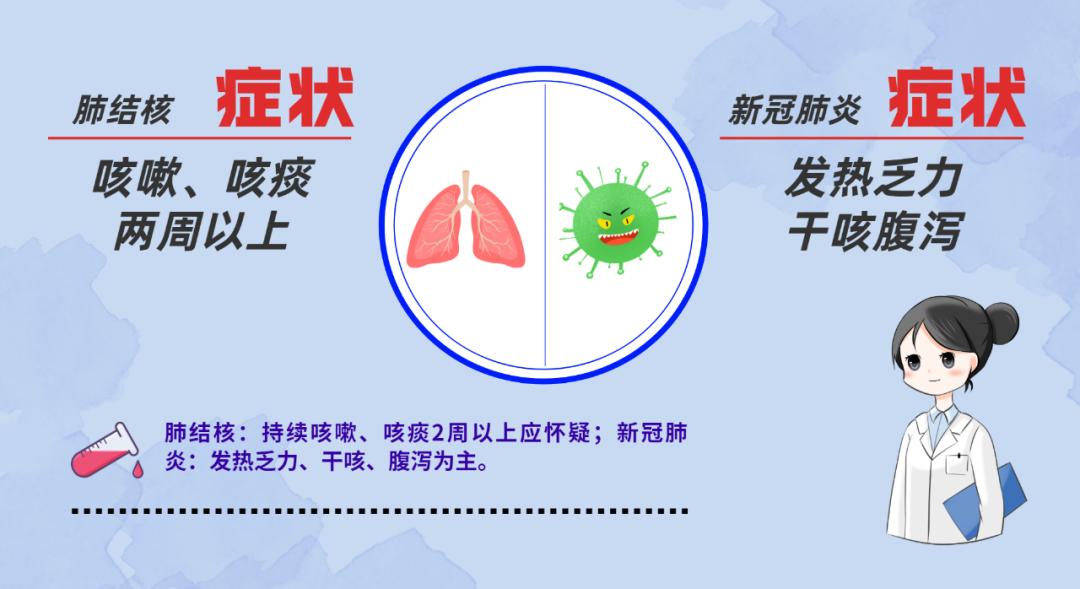

在这样一个

全民关注新冠的特殊时期

我们千万莫把

肺结核当作新冠肺炎

而延误了结核的诊治

一起来了解结核病!

不同结核病的症状有哪些?

1.肺部结核。咳嗽、咳痰超过2周,出现咯血或痰里带血丝是肺结核的主要症状。此外,胸闷、胸痛、午后低热、夜间盗汗、全身无力、食欲减退或体重减轻等也是肺结核的常见症状。